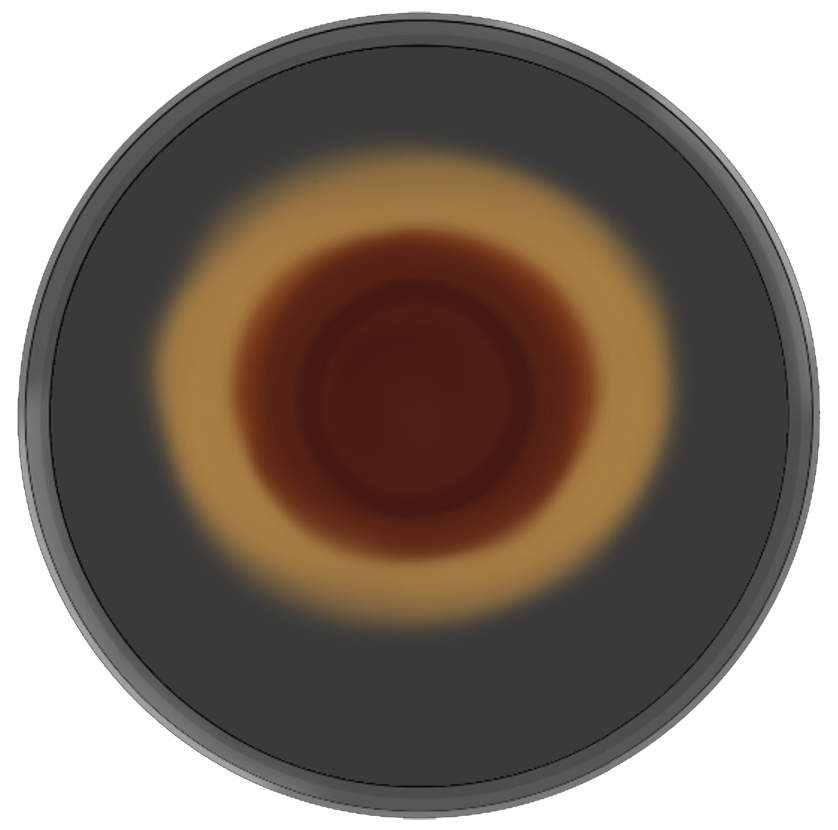

Tiene un crecimiento pausado, se observa el crecimiento de colonias aproximadamente a los 10 a 14 días a una temperatura de 25 a 30°C. El aspecto en la superficie se observa una colonia algodonosa o vellosa color blanquecino o cremoso. El aspecto posterior de la colonia tiene la característica de presentar un color rojo vino o en algunas ocasiones púrpura. Para un mejor análisis y crecimiento se toma en consideración el uso de medios como agar maíz o papa dextrosa agar. (29)